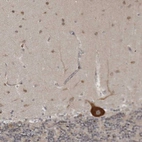

Immunohistochemistry analysis in human testis and skeletal muscle tissues using HPA020339 antibody. Corresponding ATXN2 RNA-seq data are presented for the same tissues.